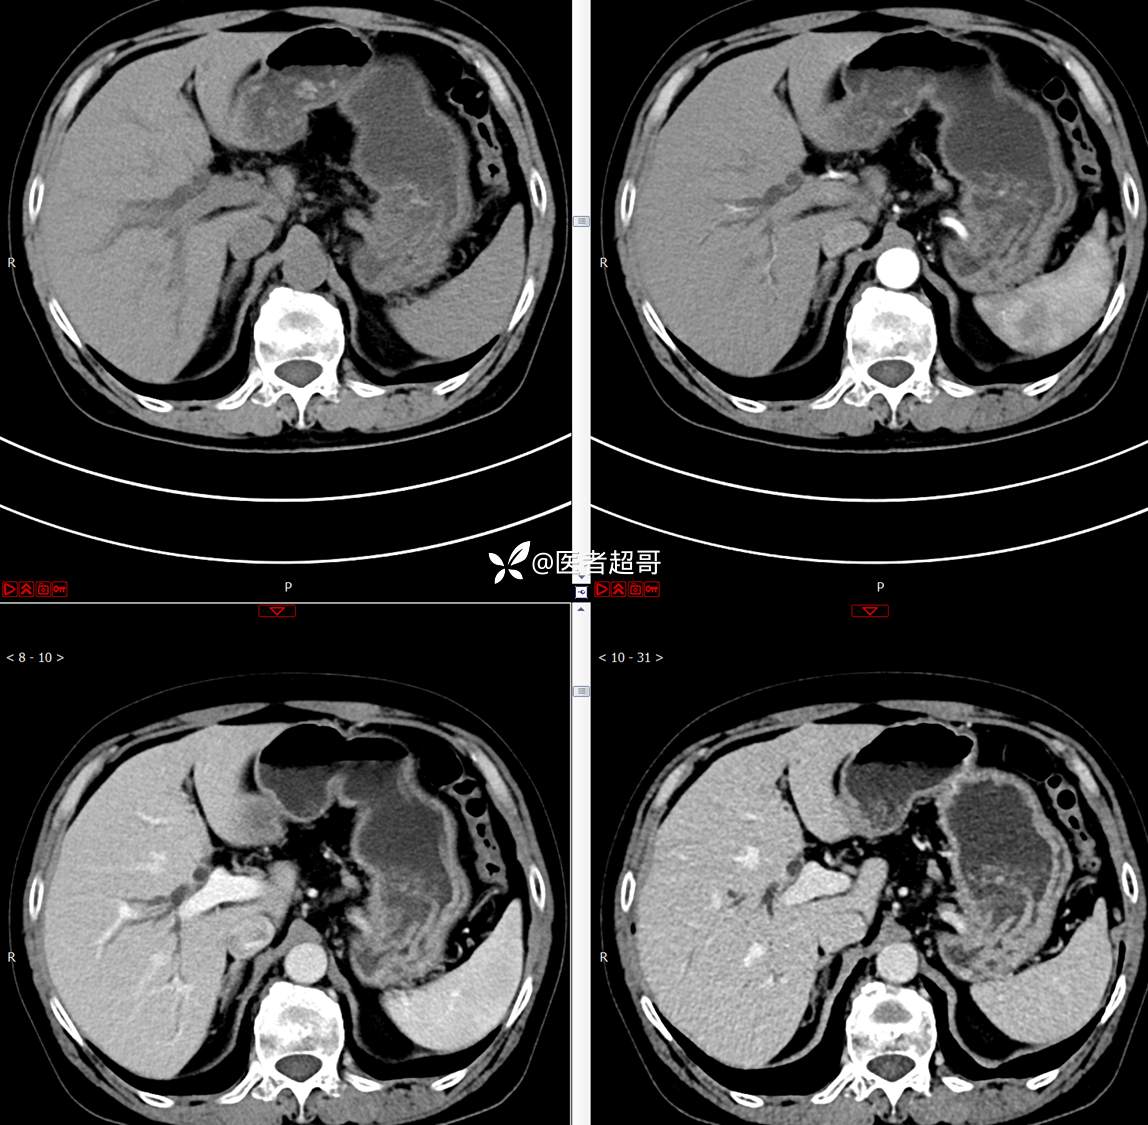

【影诊笔记772】腹痛就诊,发现肾脏病变,CT、MRI齐全,请高诊!

主 诉:间断腹痛15天

现病史:患者15天前无明显原因及诱因出现腹部疼痛不适,呈间断性钝痛,右下腹为著,无尿频、尿急、尿不尽,无发热、寒战,无腹胀。于市中心卫生院住院治疗,超声示:胰头低回声包块,胆系扩张,左肾囊肿,胆囊壁毛糙,胆囊内胆汁淤积。患者为求进一步诊治,遂以“肾盂肿瘤”收入院,患者自发病以来,神志清,精神可,饮食睡眠可,大便无明显异常,近期体重无明显增减。